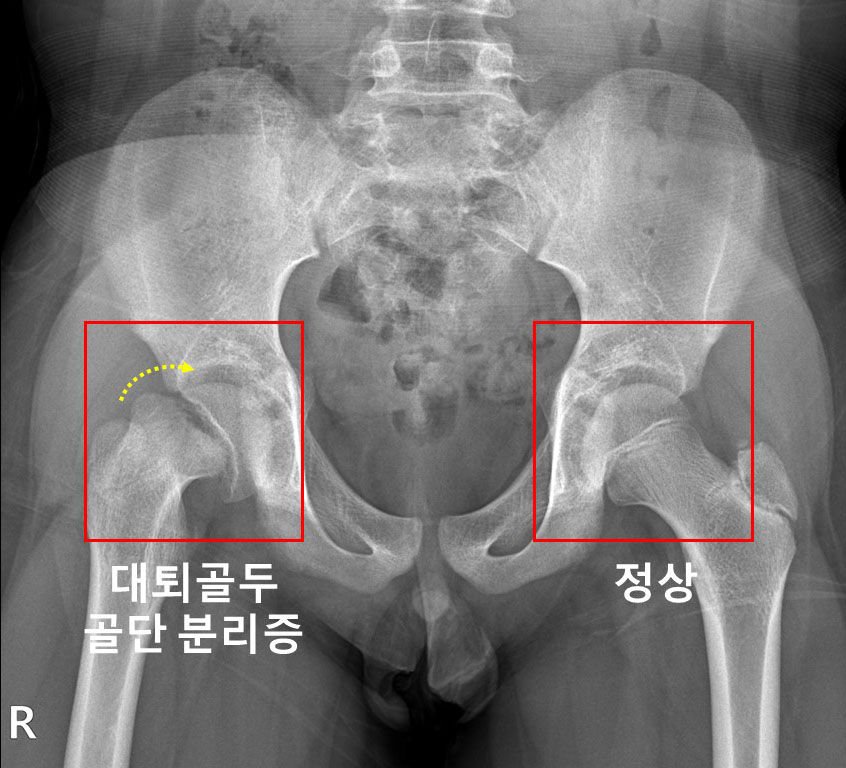

우측 고관절에 대퇴골두 골단 분리증 및 무혈성 괴사가 발생한 소아청소년 환자의 X-ray

[사진] 우측 고관절에 대퇴골두 골단 분리증 및 무혈성 괴사가 발생한 소아청소년 환자의 X-ray

대퇴골두 골단 분리증은 대퇴골 위쪽 성장판 부위에서 대퇴골두와 그 아래의 뼈가 특별한 외상 없이 분리되는 병이다. 진단이 지연될 경우, 대퇴비구 충돌증후군 혹은 대퇴골두가 썩는 대퇴골두 무혈성 괴사가 발생할 수 있다.